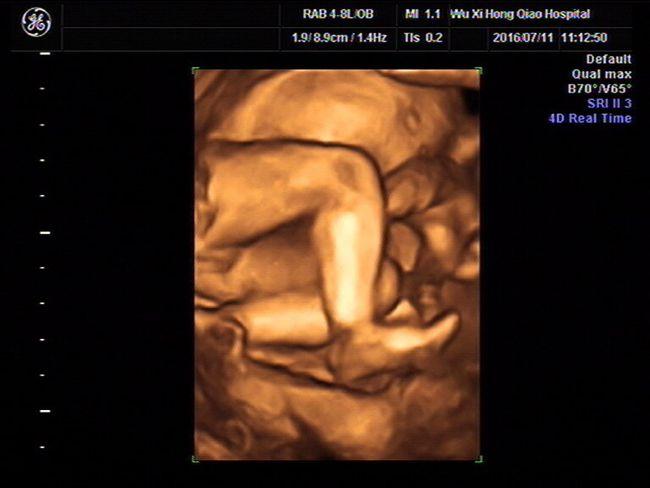

女宝的四维图器官,四个月女宝器官b超图

通过四维可以清晰看到的胎儿性别照片您懂了吗

今天四维顺利通过,大家帮我看(⊙o⊙)看男宝女宝

确认女宝四维图

看四维猜性别

四个月女宝器官b超图

女宝宝四维图片

生女儿的四维彩超图片

女宝的四维图

四维彩超女孩清晰图

四维女宝宝器官图片